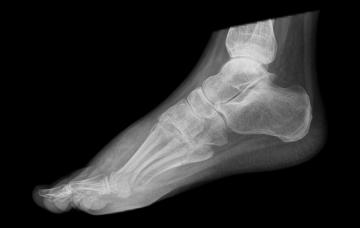

Diagnóstico de la fascitis plantar

Para diagnosticar la fascitis plantar, el médico buscará evidencias de hinchazón, enrojecimiento y sensibilidad a la presión. Conoce qué pruebas se realizan.